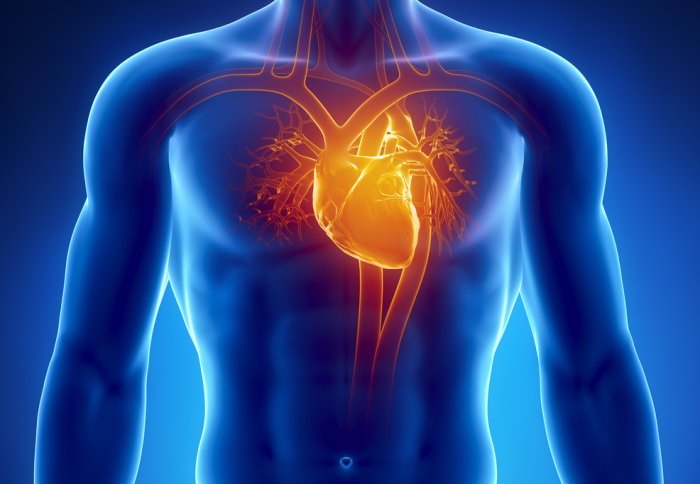

The endothelium is the lining of cells around the blood vessels, lack of dilation in which is known to be a major cause of heart strokes.

The endothelial function of all the participants was tested before they drank the energy drink to have parameters for comparison. Then the participants were again tested 90 minutes later. The scientists revealed that the blood vessels of the students had narrowed by half after the consumption of the energy drinks.

When the blood vessels shrink from their original size, it becomes difficult for the heart to perform circulation and this can lead to heart strokes.